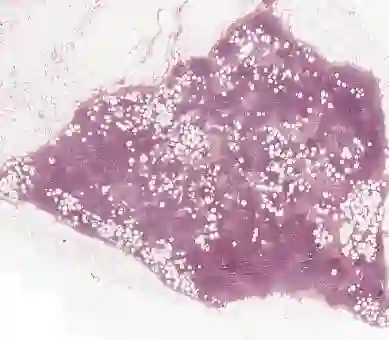

Multiple Instance Learning (MIL) is widely used in analyzing histopathological Whole Slide Images (WSIs). However, existing MIL methods do not explicitly model the data distribution, and instead they only learn a bag-level or instance-level decision boundary discriminatively by training a classifier. In this paper, we propose DGMIL: a feature distribution guided deep MIL framework for WSI classification and positive patch localization. Instead of designing complex discriminative network architectures, we reveal that the inherent feature distribution of histopathological image data can serve as a very effective guide for instance classification. We propose a cluster-conditioned feature distribution modeling method and a pseudo label-based iterative feature space refinement strategy so that in the final feature space the positive and negative instances can be easily separated. Experiments on the CAMELYON16 dataset and the TCGA Lung Cancer dataset show that our method achieves new SOTA for both global classification and positive patch localization tasks.